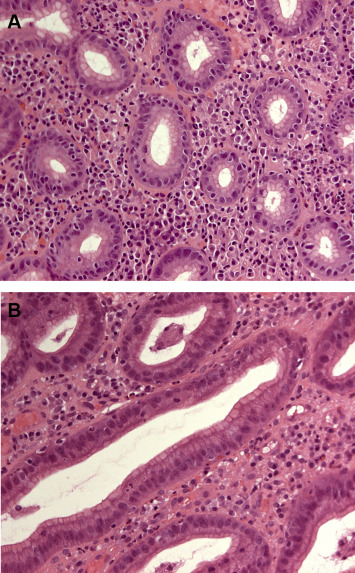

Submucosal tissue was virtually invisible in histological sections regardless of the group. The ratio of the gastric epithelium to the stroma in the gastric mucosa from either the controls or the ulcers with delayed healing was comparable (Fig. 1 ). Hemorrhages in tissue and crushing artifacts related to biopsy were limited.

Histological examination of specimens taken from the ulcer margin show a similar ...

Figure 1.

Histological examination of specimens taken from the ulcer margin show a similar morphology of the gastric mucosa in the (A) normal and (B) delayed healing groups. Hematoxylin and eosin stain, 200×.